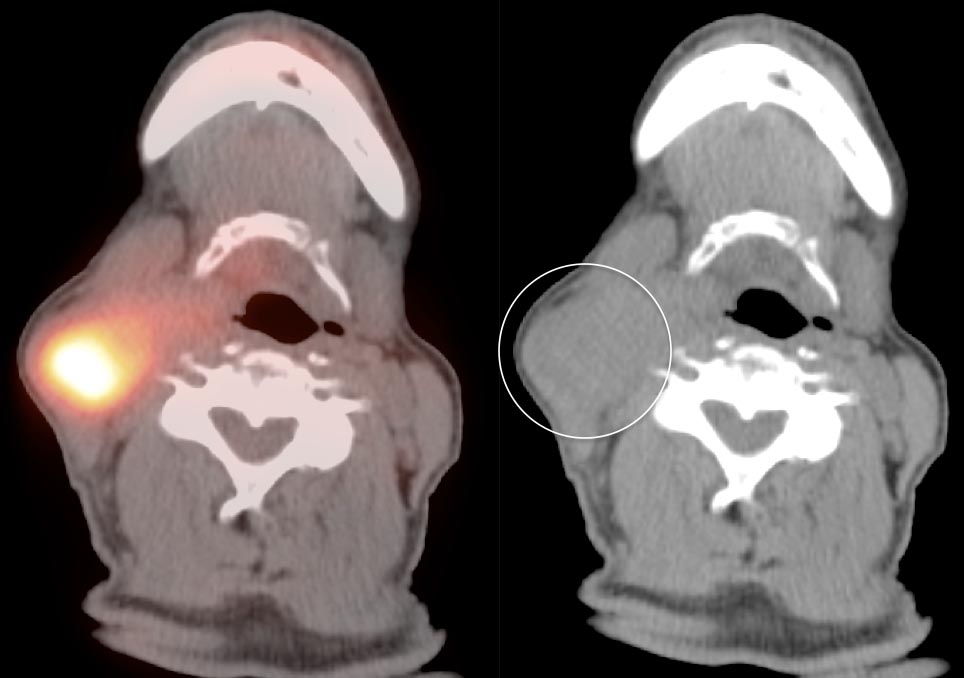

Focal, eccentric or asymmetric uptake along a portion of the tongue base should always raise a concern for a primary tongue base cancer, and requires direct visualization by a clinician (addressed in detail, here).